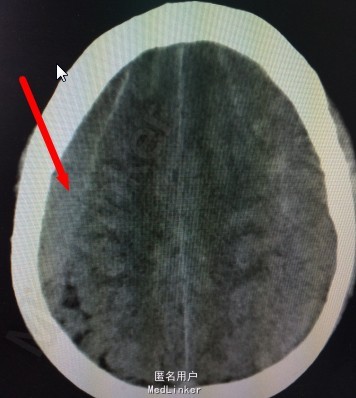

患者,男;62岁,主诉:反复阵发性头痛2个月。现病史:患者2个月劳累后突发性头痛,疼痛首先位于双侧枕部,逐渐累及双侧额、颞部,每次疼痛约30分钟,平卧后可稍缓解,伴恶心,呕吐,为喷射性,呕吐物为胃容物;无昏迷,肢体活动可,无大小便失禁,曾就诊于当地医院,给予保守治疗约20天,症状未见明显缓解;1周前患者来我院就诊,行头颅MRI示,双侧额、颞、顶、枕硬膜下血肿,可疑右顶血管畸形。现为求进一步诊治而入我院。

初步诊断:慢性硬膜下血肿 处理:慢性硬膜下血肿钻孔引流术

慢性硬膜下血肿是指颅内出血血液积聚于硬脑膜下腔、伤后三周以上出现症状者。目前对于血肿的出血来源和发病机理尚无统一的认识。其发生率约占颅内血肿的10%,血肿常发生于额顶颞半球凸面,积血量可达100-300毫升。临术表现以颅内压增高为主,头痛较为突出,部分有痴呆、淡漠和智力迟钝等精神症状,少数可有偏瘫、失语和局源性癫痫等局源性脑症状。 首选的方法是钻孔引流,疗效堪称满意,如无其他并发症,预后多较良好。